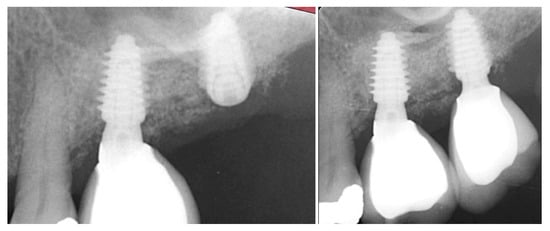

Figure 8.

Failing 1st and 2nd molars related to periodontal bone loss (left), the site following 10 weeks of healing to allow soft tissue closure over the ridge (middle) and a radiograph demonstrating the available bone between the crest and sinus for implant placement (right).

At 10 weeks post-extraction, the patient presented, and consent forms were reviewed and signed for grafting and implant treatment. Soft tissue had healed, closing the site with keratinized tissue (Figure 8, middle). A radiograph was obtained to check what available bone was present at both sites (Figure 8, right). Sufficient height was available to place an implant at the 1st molar site in conjunction with a crestal sinus augmentation, but insufficient height was present at the 2nd molar site which would require grafting to increase crestal height and later implant placement could be performed at that site.